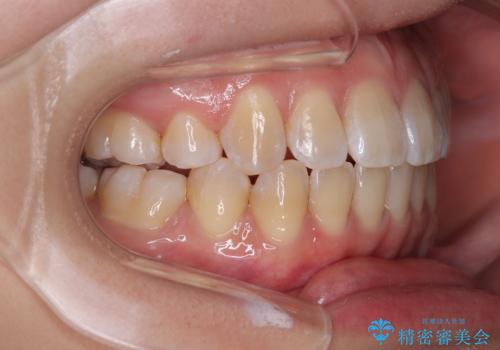

- 上下顎前歯部の非接触(開咬)と下顎のデコボコを主訴に来院された患者様です。

右側上下と左上の小臼歯が一本ずつ少なく、さらに骨格的な左右差もあり上下の真ん中の位置がずれています。

下顎のデコボコの解消と、真ん中の位置を改善するために左下の小臼歯を抜歯することとしました。

また、開咬を改善するため臼歯部にアンカースクリューを用いて圧下する力をかけていきました。

舌を突出する癖があり、それにより開咬が悪化したり、後戻りの原因になるため、舌のトレーニング(MFT)も行いました。